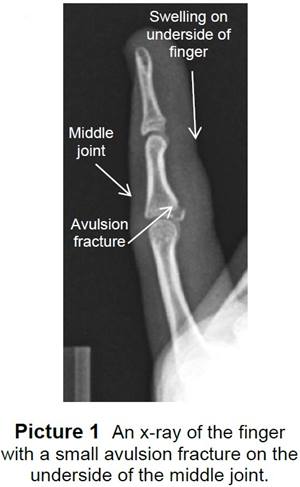

• When a finger bends back or sideways too far, the volar plate and one or both of the collateral ligaments can be torn. Sometimes, the injury may break off a small piece of bone. This type of broken bone is called an avulsion fracture (Picture 1).

To know if your child has a sprain or an avulsion fracture, the doctor or health care provider will order an X-ray of the finger.